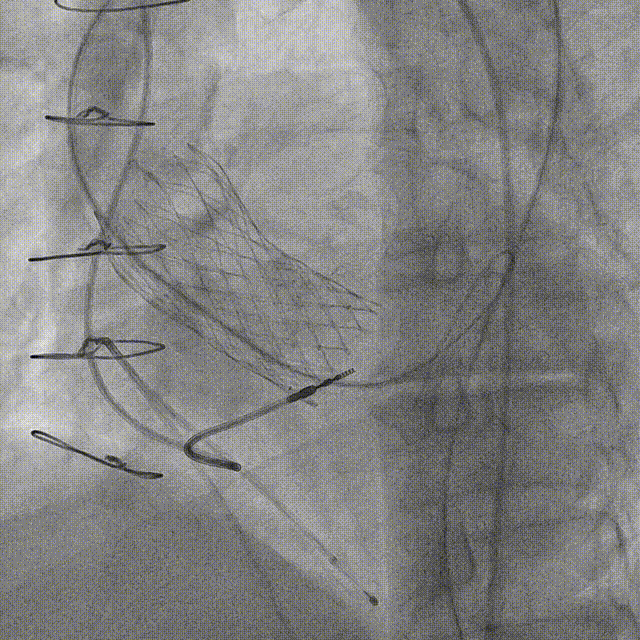

2012年TAVR操作视频回顾:

22mm球囊扩张。

2012年植入26VenusA-Valve瓣膜植入后造影。